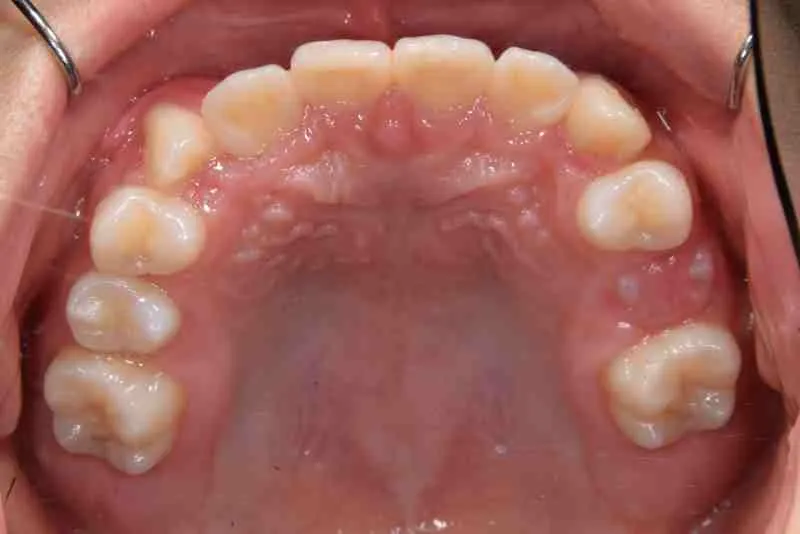

• 初診

初診時年齢 小学校2年生 (女性) 主訴 受け口・がたがた

診断名 埋伏歯・反対咬合・叢生 装置名

特徴 ゆがんで生えている

上の歯と下の歯で舌をはさむ癖がある

状態 永久歯が生える隙間がない(叢生)

受け口(下顎前突/反対咬合)

歯が埋まっている/歯がない(埋伏歯)

受け口で、ガタガタが有りました。

レントゲンを撮ってみると犬歯の萌出方向がずれていました。

初診